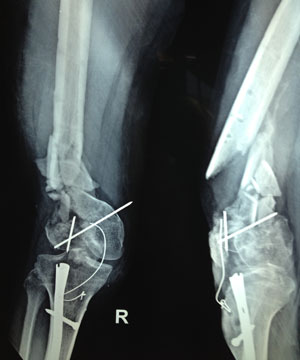

Polytrauma describes multiple complex injuries of the brain and body typically caused by explosive blasts from car bombs, shells and flying shrapnel. The condition is commonly characterized by multiple head injuries, vision and hearing loss, nerve damage, multiple bone fractures, unhealed body wounds and infections - either of which can be life threatening. Others injuries may include severed limbs or spinal cord damage with the majority of patients experiencing some amount of traumatic brain injury. The complexity and severity of injuries sustained may also lead to emotional or behavioral challenges. In recent years, more soldiers and service men have been diagnosed with polytrauma as modern advancements have allowed victims of multiple blast wounds to be rescued from battle instead of dying in combat. Now, more soldiers and civilians on foreign soil are surviving massive injuries and can receive the medical care they need after returning home.

HOW IS POLYTRAUMA TREATED?

If you require polytrauma care, you'll need more than one doctor working on one condition. A comprehensive system of care is required for soldiers suffering from polytrauma. Based on your specific needs, a team of healthcare professionals will design a regimen of care that heals injuries and minimizes pain but also addresses your psychological and emotional challenges. The cornerstone of this comprehensive approach is rehabilitation. Prosthetic limbs and physical therapy may help you regain mobility while other therapies may help you regain your speech, memory and motor skills.